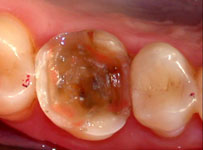

Fig. 11

Molde depois de removido juntamente com os pinos plásticos que reproduzirão os orifícios.

Fig. 12

Troquel de trabalho articulado ao modelo mestre, onde se pode visualizar os quatro orifícios reproduzidos pelos pinos de nylon.